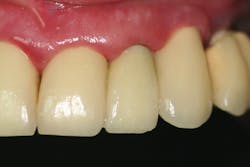

Third visit: The final crown was delivered.

The implant was allowed to heal for two months before impressions were taken. The final zirconia crown was delivered two weeks later (figure 6).

With his previous implant tooth replacements, this patient had an arduous recovery. He experienced severe postsurgical pain and had to endure prolonged treatment time because of his challenging recovery. After this most recent implant placement, the patient reported to our office that he had absolutely no postoperative discomfort, no prosthesis complications, and he was very impressed by the entire experience. He reported that he did not need any postsurgicalThis case study shows that implant placement can be successful even in patients with difficult medical issues if the clinician adheres to the correct protocols and uses a precision implant system.